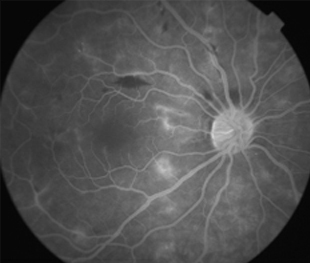

Angiografía OI

- Angiografía: teñido arterial, escape capilar, más tardíamente, no perfusion arteriolar y venular con teñido de las paredes vasculares y dilatación venosa.